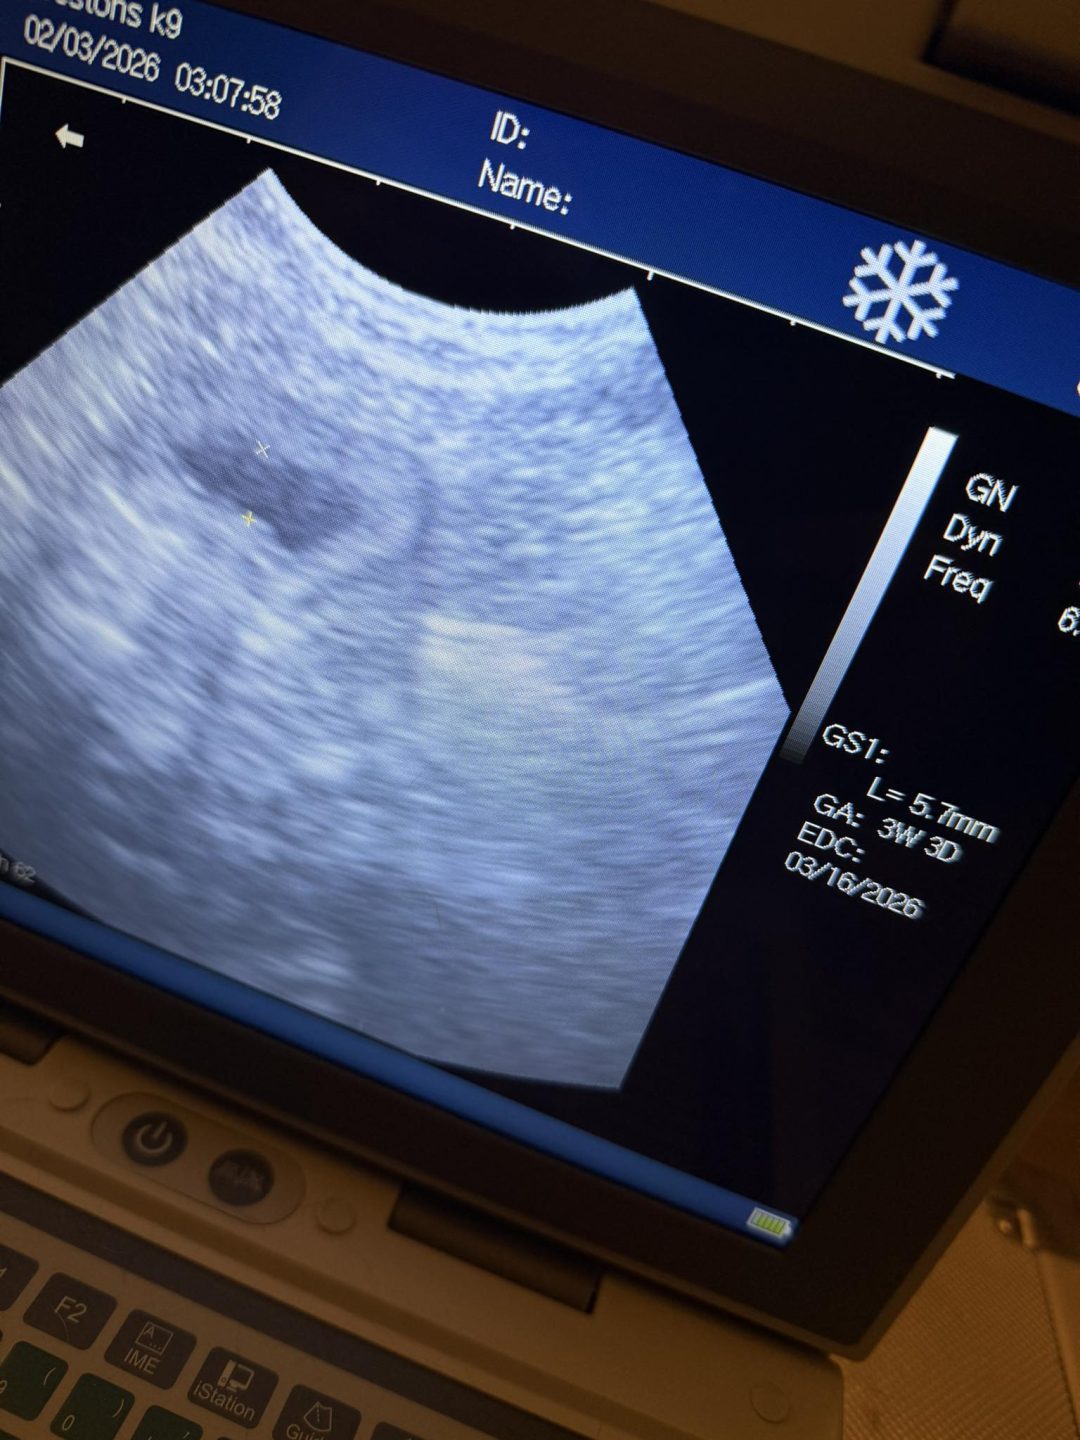

Confirmation ultrasound scan carried out on a mobile visit in Preston this evening

On finding out this girl could be only about 3 weeks pregnant

Sacs could be seen, but no embryos inside, either, being so early in pregnancy